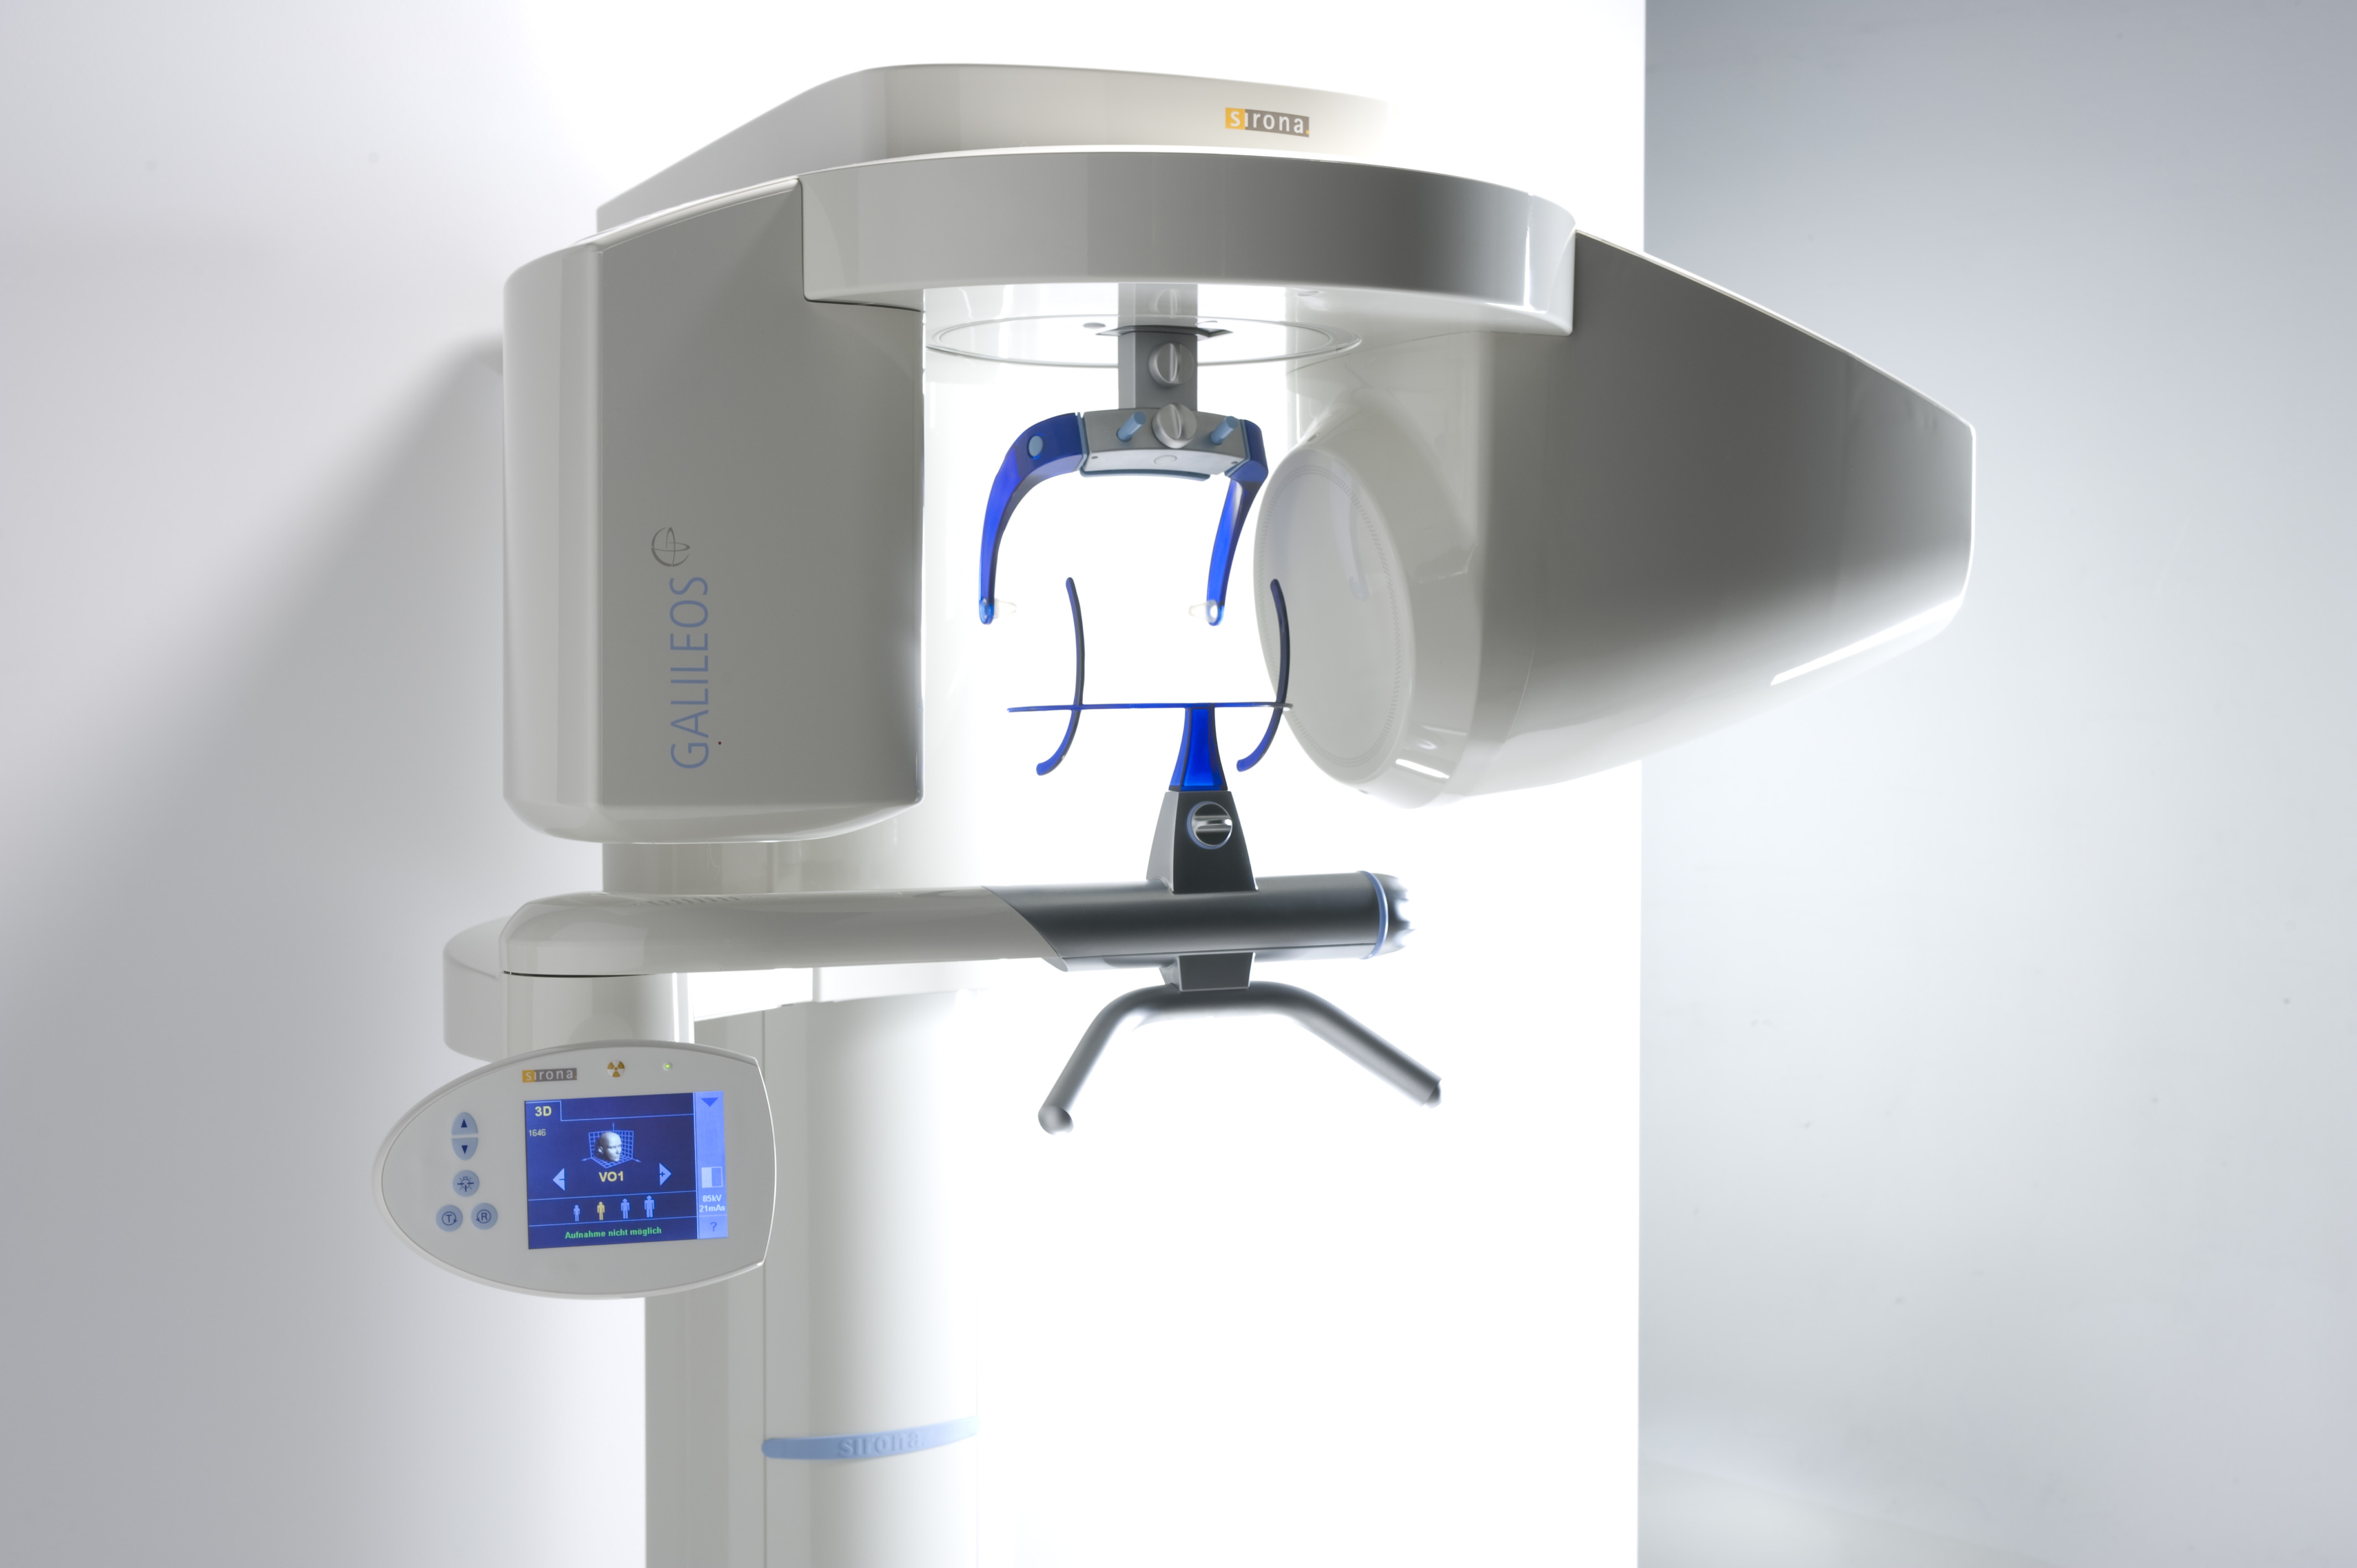

We want you to receive the best dental care possible and that is why Dr. Song invested in the latest technology in dental diagnostics, the Galileos® 3D Dental Conebeam. Cone Beam Computed Tomography (CBCT) allows 3-D visualization of the oral and maxillofacial complex from any plane. The 14 second scan offers a large volume for every display type – 3D, panorama, CEPH, and cross sectional (TSA) slices with smaller radiation than that produced by medical CT. The radiation is the equivalent of 4 bitewings.

• Lowest radiation possible

• Quick, easy and comfortable scan of the mouth, face and jaw

• Immediate virtual diagnosis and treatment planning in one visit

• More security and less time during surgery

• Easy sharing of images with referring doctors

Understanding the delicate nature of Implant Surgery, Dr. Song has incorporated guided implant surgical procedure for all her implant needs. Using 3D cone beam CT scanner (Galileos) to transfer image of the dental and soft tissue topography in and around the implant space into a 3D virtual image of a patient's jaw, Dr. Song can safely and accurately plan and create individually customized surgical guide that is specific to each implant case. This process eliminates the guessing game and significantly reduces room for error in all types of implant surgery. At this time, once a "scan stent" or implant design is submitted to SICAT, each individual surgical guide is produced in Germany and delivered directly to Dr. Song to complete the surgery. However, in the near future, with the advent of technology it will be soon possible for Dr. Song to mill the surgical guide directly from her office, saving time and money for her patients.